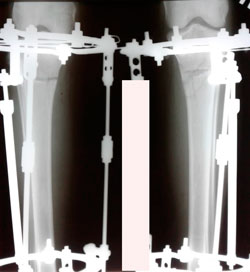

Исходник - 24 года.

Дата операции - 05.11.2020

Диагноз: Варусная деформация голеней + Ротация с обеих сторон.

на фиксации